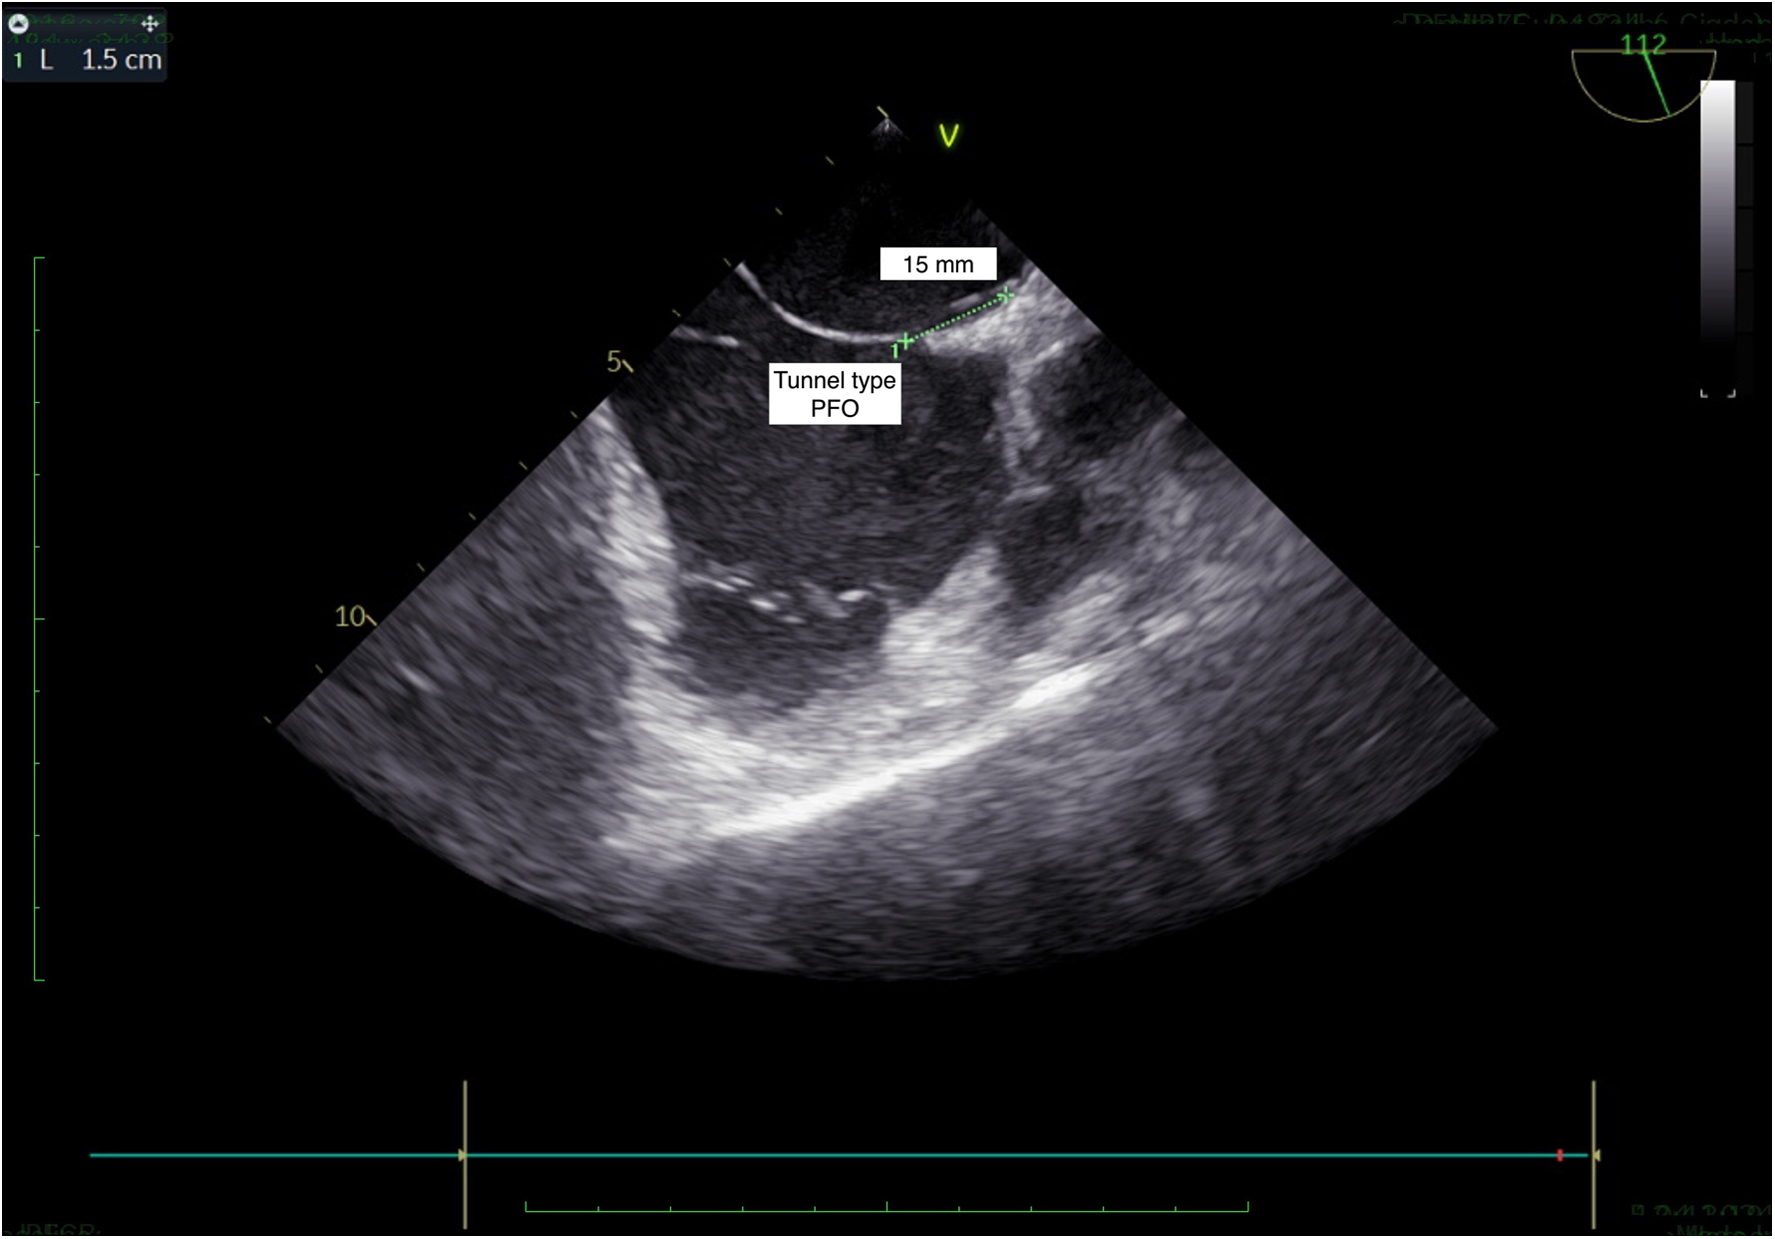

Figure 2

TEE, bicaval view: tunnel type PFO.

If the septostomy point is determined by taking both A-P and bicaval sections, it provides a more accurate anatomical assessment, allowing for the correctly sized closure device to be selected. When the septostomy point was made inferiorly, the correct device size was selected without increasing the overall device size, ensuring proper closure and reducing the risk of a residual shunt (Figures 1A, 2–5). As shown in Figure 1B, in the A-P section, the distance between the septostomy point and the tip of the PFO is 8 mm, whereas in the bicaval section of the same patient, this distance is 13 mm (Figures 1C, 2–5). If the device had been selected by taking images from a single section (A-P), a small device would have been selected and a residual shunt would have been left.

(A) When the septostomy point was placed lower (9 mm), the correct device selection was made possible without increasing the device size. If the device had been selected by taking images from a single section (A-P), a too-small device would have been selected and a residual shunt would have been left. (B) In the anterior-posterior section, the distance between the septostomy point and the tip of the PFO is 8 mm. (C) In the bicaval section of the same patient, this distance is 13 mm.